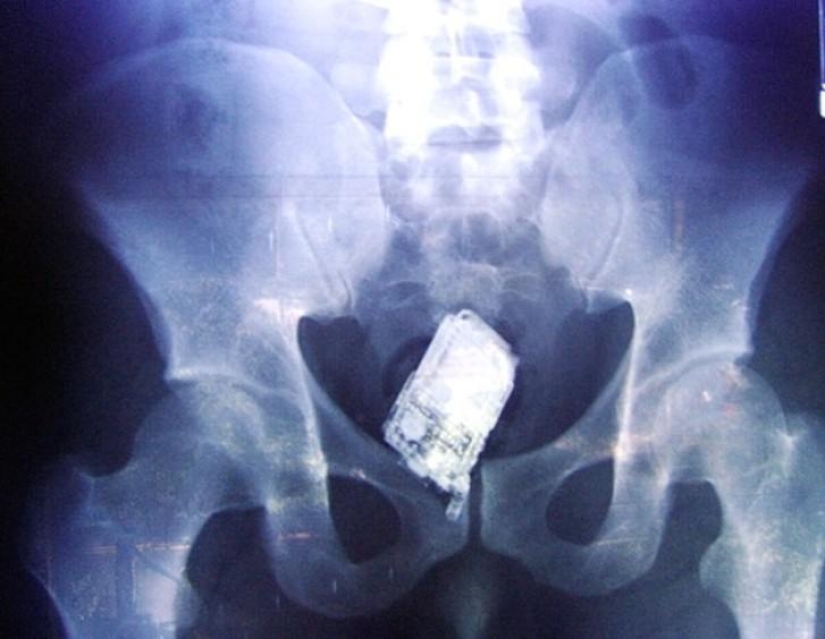

20. Teléfono móvil.